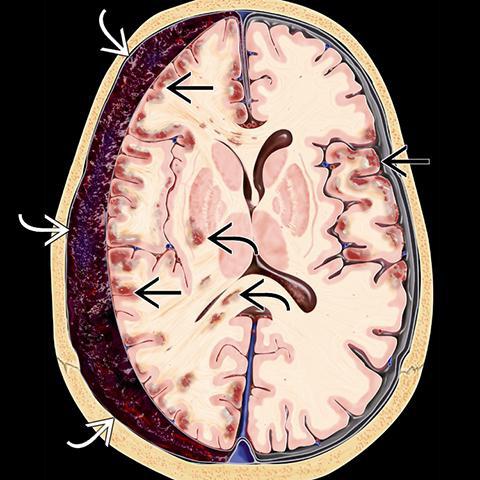

Внутричерепные кровоизлияния у новорожденных презентация - 92 фото